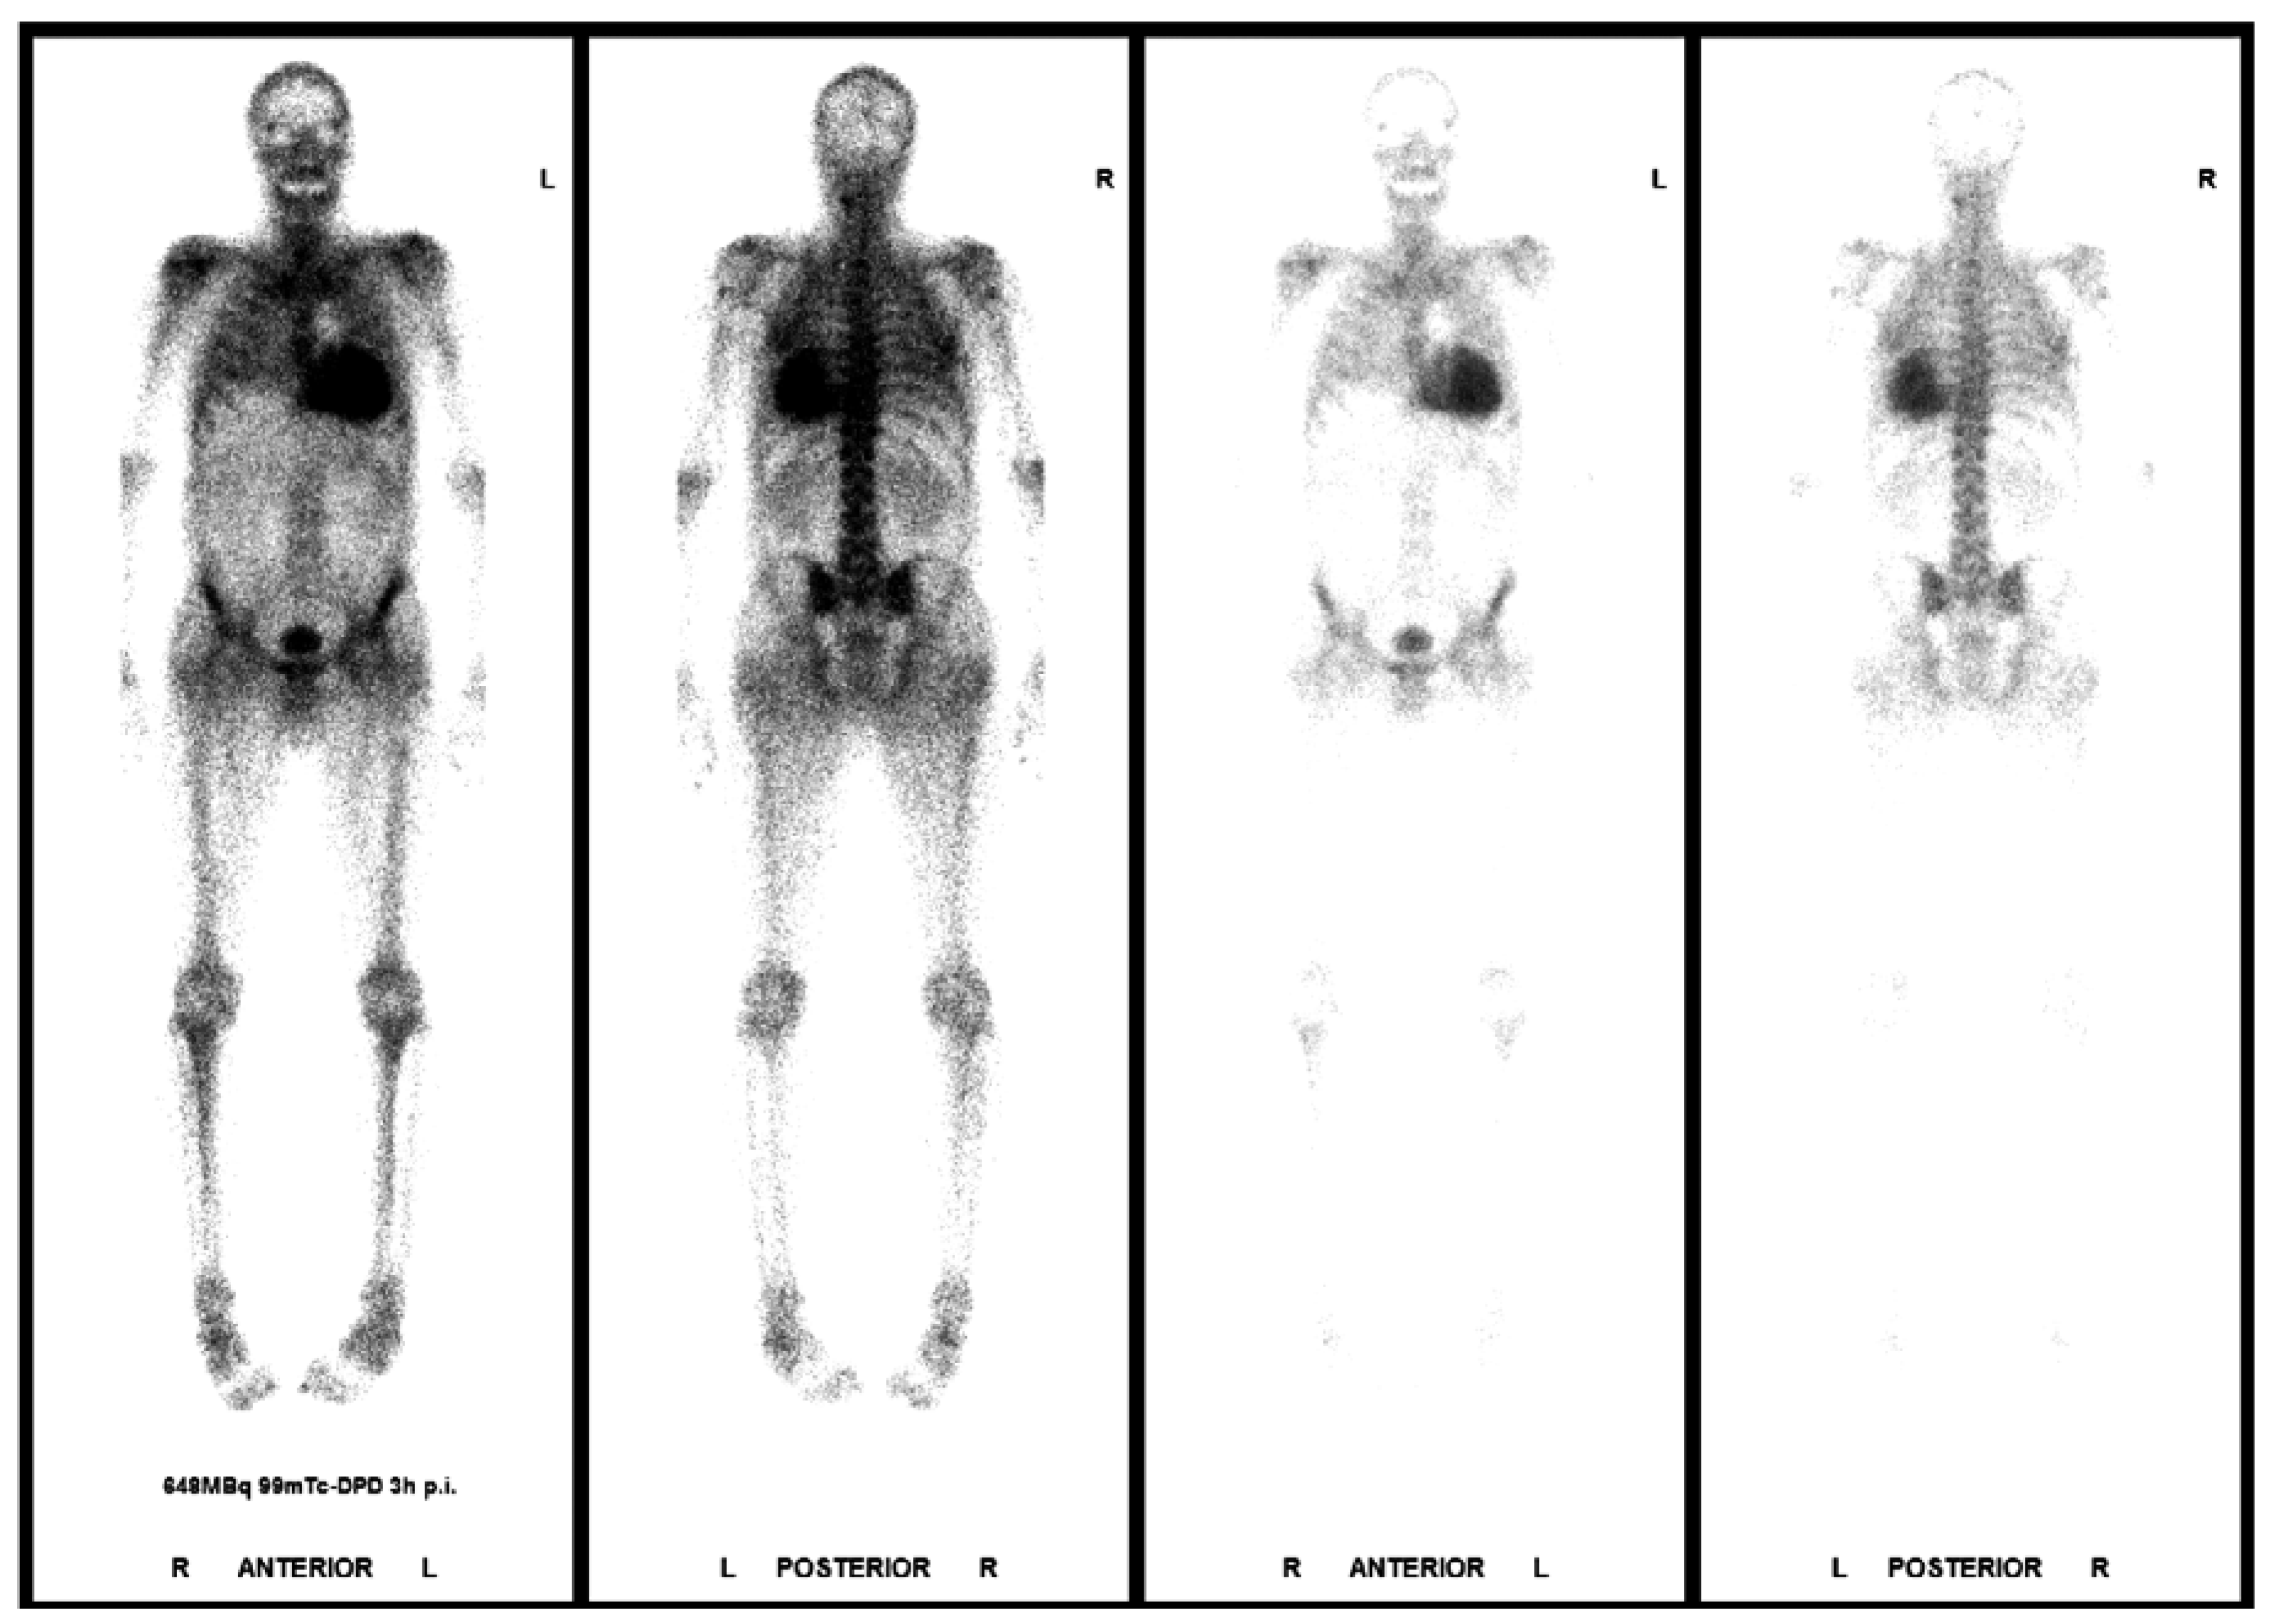

- Biopsy is the gold standard, confirming the presence of amyloid with congo red dye and green birefringence in cross-polarised light; however, TTR cardiac amyloidosis can be diagnosed with bone-scintigraphy alone in the absence of a monoclonal gammopathy.